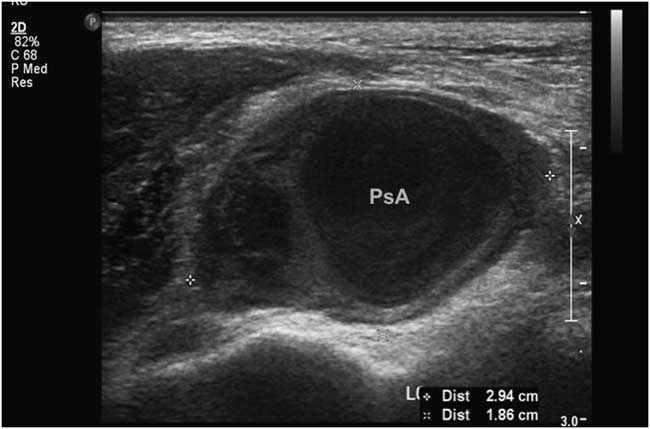

Duplex ultrasound performed in the radiology suite the following morning (eighth day after initial injury) revealed a left anterior tibial artery pseudoaneurysm at the level of the ankle measuring 2.94×1.86 cm, with a 5.6×1.9 cm hematoma overlying the lateral ankle (Figures 2 and 3). Diagnostic ultrasound images of the lesion were obtained by scanning over skin marked with the large X (Figure 1), corresponding to the area of maximal swelling and pain. Distal flow was identified within the dorsalis pedis artery. The diagnosis was confirmed with CT angiography, which demonstrated a large pseudoaneurysm arising from the dorsal-lateral aspect of the proximal dorsalis pedis artery. Of note, after imaging the patient was re-examined and found to have an easily audible bruit in the area of the anterolateral ankle and dorsum of the foot, overlying the pseudoaneurysm.

Figure 2 2D ultrasound image showing maximal diameter of anterial tibial pseudoaneurysm.

While angiography remains the gold standard for diagnosis and treatment planning, duplex ultrasound is the accepted modality for initial non-invasive imaging.Reference Shah, Fischman and Marin 11 , Reference Webber, Jang and Gustavson 16 Sensitivity and specificity of duplex ultrasonography in the diagnosis of pseudoaneurysm are estimated at 94% and 97%, respectively.Reference Coughlin and Paushter 19 Bedside diagnosis of post-traumatic arterial pseudoaneurysms of the face and lower limb, using point-of-care ultrasonography performed by the ED physician, has indeed been described in a few case reports of single patients.Reference Goksu, Kucukyilmaz and Soyuncu 18 , Reference Goksu, Yuruktumen and Kaya 20 - Reference Jenq, Panebianco and Lee 22 The bedside technique most commonly described consists of linear ultrasound probe placement directly over the area of maximal swelling (or bruit/thrill, if present).Reference Goksu, Kucukyilmaz and Soyuncu 18 , Reference Goksu, Yuruktumen and Kaya 20 The anechoic pseudoaneurysm cavity may be pulsatile and is commonly surrounded by hypoechoic thrombus (Figure 2).Reference Goksu, Kucukyilmaz and Soyuncu 18 , Reference Jenq, Panebianco and Lee 22 This sonographic appearance may closely resemble that of an abscess cavity with debris.Reference Abdi, Armijo and Seif 21 The use of color Doppler is particularly valuable in differentiating the two. Characteristic findings of pseudoaneurysm include bidirectional blood flow in the pseudoaneurysm neck, pulsatile flow in the cavity (Figure 3), and the “yin-yang sign” (swirling blood in the pseudoaneurysm resembling the ancient symbol).Reference Goksu, Yuruktumen and Kaya 20 The accuracy of bedside ultrasound in the diagnosis of arterial pseudoaneurysms has not yet been elucidated.